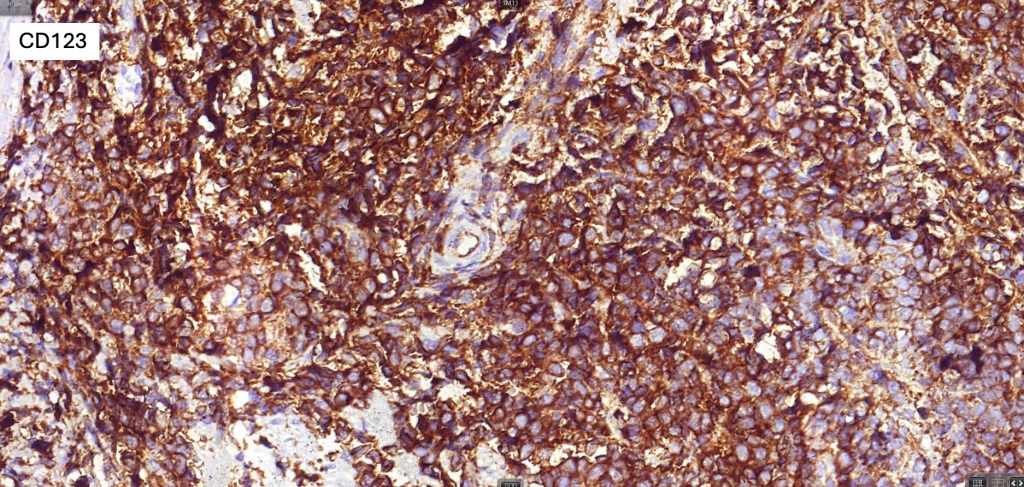

. CD4, CD43, CD56, CD123, CD303, TCF4 & TCL1 +ve

. Variable CD68, CD7, CD33 & TdT +ve